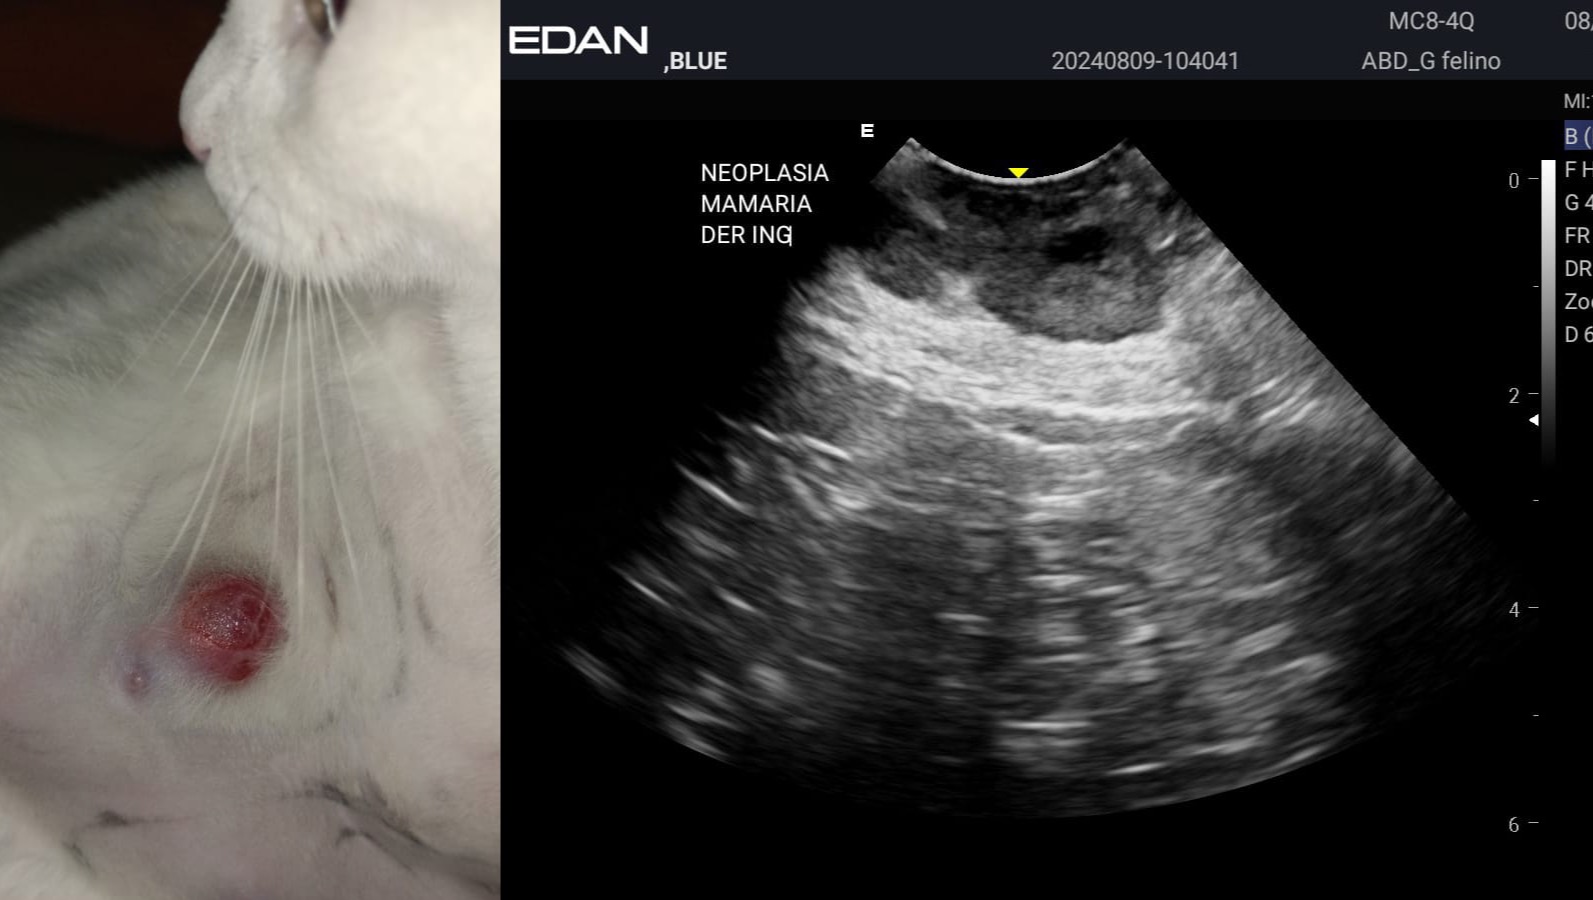

Thankfully we were recommended an oncology specialist, who was able to size her up right away. She believes the mammary growths are most likely malignant, and she needs a radical bilateral mastectomy to survive. After removal, these tumours will be biopsied in order to proceed with the proper kind of chemotherapy.

The money will go to her surgeries (they will be split in two due to the high risk of removing everything at once), her post-op, the biopsy and the following treatment. Her most recent tests and imaging suggest that the tumours have not metastasized yet but, even though she’s tough as nails, we cannot wait any longer.